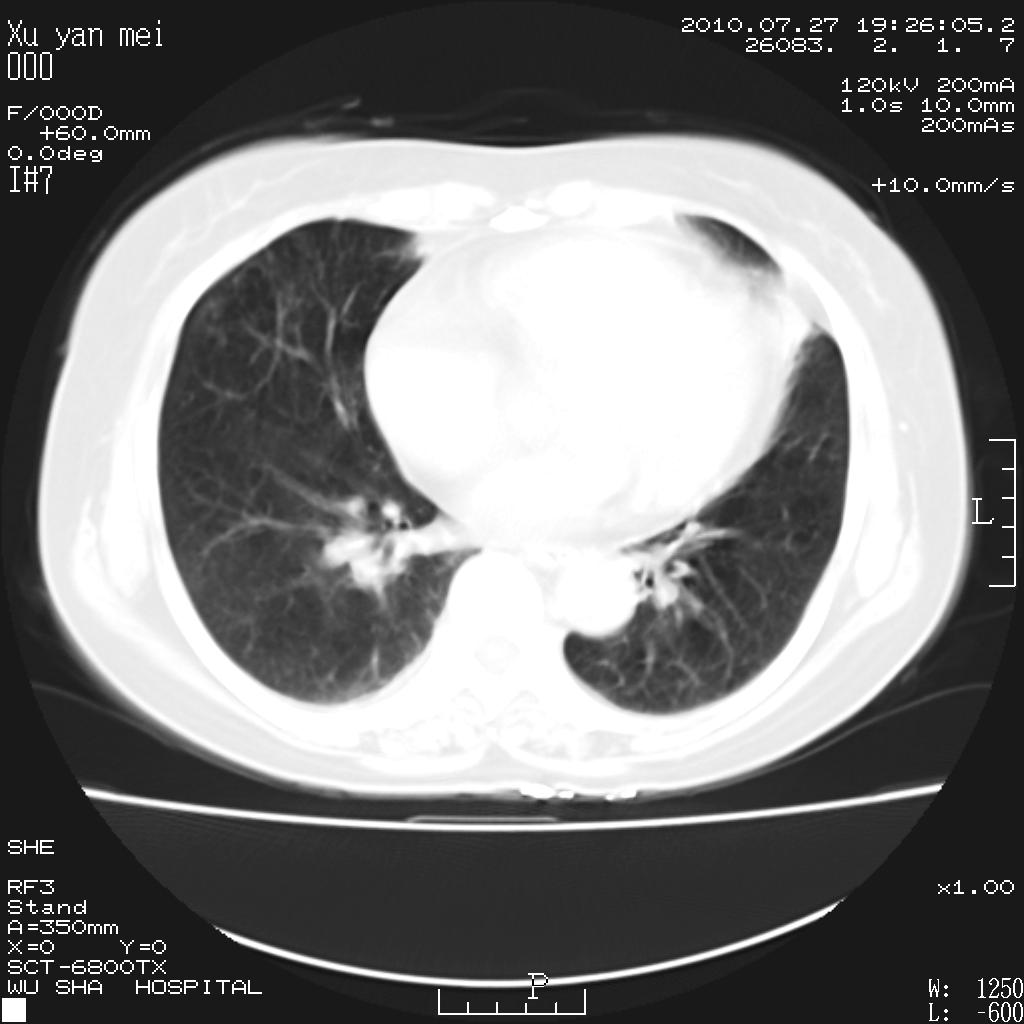

女,60岁,胸痛就诊,右肺结核?炎症?其它?(胸片右侧中上肺野确实看不到什么啊)

1)考虑两肺感染性病变;建议抗炎治疗后复查。2)双侧少量胸腔积液。

1)考虑两肺感染性病变;建议抗炎治疗后复查。2)右侧少量胸腔积液。

右侧少量胸腔积液,段性肺炎。

双肺炎症可能性大,建议抗炎后复查。右侧胸腔少量积液。双侧胸膜轻度增厚。

考虑两肺感染性病变;不除外肺栓;建议抗炎治疗后复查。